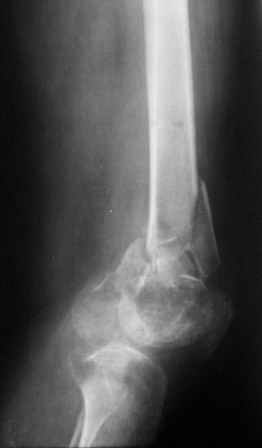

Уважаемые коллеги! Представляю на ваш суд ближйший результаты лечения.

На момент операции не было возможности запечатлеть увиденное, поэтому попытаюсь пересказать.

Первое что пришло в голову по аналогии очень похоже на асептический некроз головки бедра когда головку извлекают при эндопротезировании.Хрящ внутреннего мыщелка бедра был отслоен и изменен,сам мыщелок проминался под пальцем. От блокирования стяжкой отказались. Можно ли это расценить как асептический неркоз внутреннего мыщелка в результате первичной травмы?

Леонид Соломин писал о случае с пателлофеморальным синдесмозом(спасибо), но к сожалению сообщение пришло уже после операции.Прежде мы не встречались с подобным.Во время мобилизации после артролиза, отсечения интремедиуса попытались согнуть колено: хрящ надколенника остался на мыщелках бедра(!). В результате приняли решение удалить надколенник.

Раннее послеоперационное течение не очень спокойное- из раны было сукровичное отделяемое, но сейчас вроде идет на поправку(на фоне интенсивного лечения). В аттаче рентгенограммы.

Жду ваших комментариев!

Рентгенограмма симпатичная...